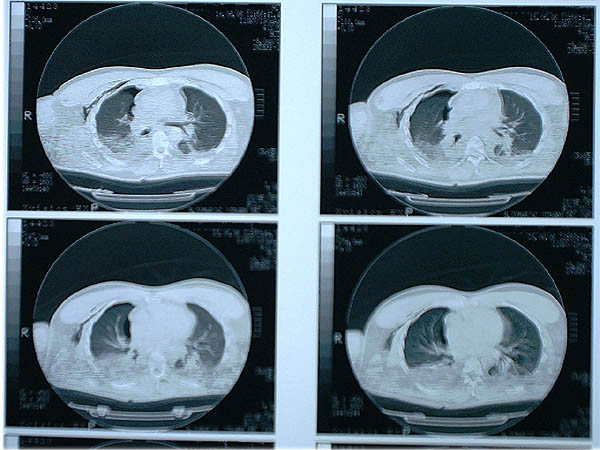

Fibrosis pulmonar. ICC.

Neumonia basal derecha.

Neumonía basal derecha.

Neumonía basal derecha

TBC pulmonar antigua

Tumoración mediastínica

APR Bronquiectasias

APR Metástasis torácicas

APR Patrón fibroso antiguo

MO Distres respiratorio del adulto por trauma.

MO Distrés respiratorio del adulto